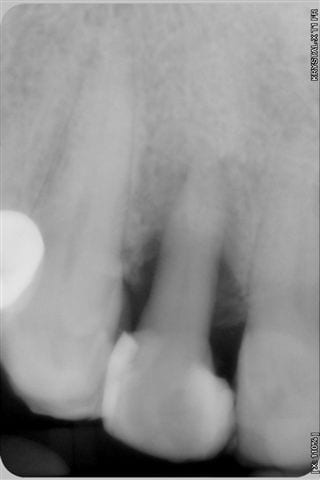

première radio le 22/07 et la 3ème aujourd'hui

Je me demandais ce qui pourrait encore vous faire douter, bingo "la première radio est plus sombre que la 3ème" eh bien en voici une prise le 22/7 en urgence et moins sombre, aurez vous encore des doutes quant au bien fondé d'un traitement conservateur laser assisté???

Désolée, mais l'implant n'est pas pour demain et j'en suis fort aise

j'ai oublié de vous dire que la dent n'est plus du tout mobile et que la gencive n'a plus d'aspect inflammatoire.